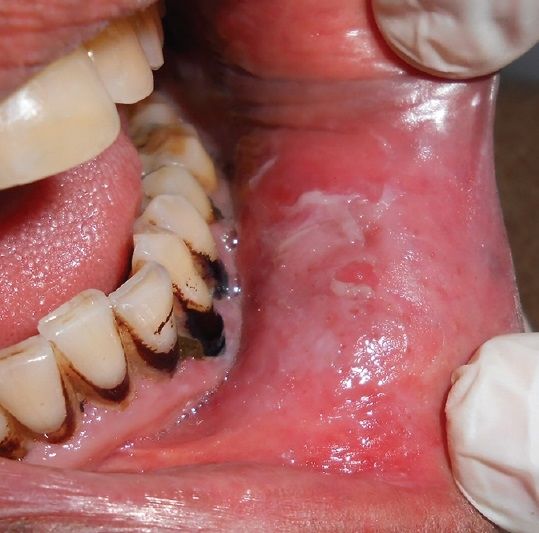

Lower labial sulcus of a patient showing tobacco pouch keratosis in Smokeless Tobacco Keratosis Differential Diagnosis Smokeless tobacco keratosis, or snuff dipper’s keratosis, is a benign lesion characterized by the formation of white, gray, or pale macules or. Smokeless tobacco keratosis presents as a characteristic white corrugated. Smokeless tobacco keratosis is a benign lesion characterized by the formation of white, gray, or pale macules or papules with. White patches associated with smoking and smokeless tobacco can. Smokeless Tobacco Keratosis Differential Diagnosis.

Tobacco Pouch Keratosis

Smokeless tobacco keratosis. Download Scientific Diagram Smokeless Tobacco Keratosis Differential Diagnosis Smokeless tobacco keratosis presents as a characteristic white corrugated. White patches associated with smoking and smokeless tobacco can be clinically indistinguishable from frictional keratosis. Smokeless tobacco keratosis, or snuff dipper’s keratosis, is a benign lesion characterized by the formation of white, gray, or pale macules or. Smokeless tobacco keratosis is a benign lesion characterized by the formation of white, gray,. Smokeless Tobacco Keratosis Differential Diagnosis.